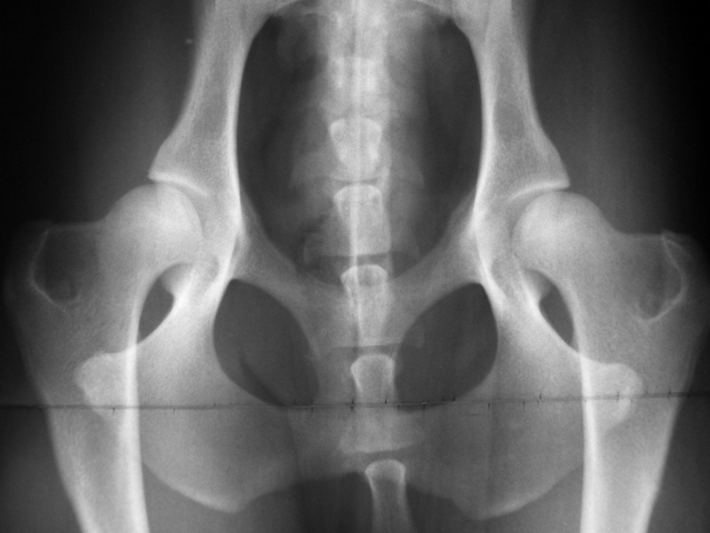

Abb. 3: Englischer Setter mit HD Grad C. Der Oberschenkelkopf ist zwar rund, rutscht aber etwas aus der Pfanne. Der vordere Pfannenrand läuft horizontal aus. Solche Hunde neigen im Laufe des Lebens zu Hüfgelenksarthrose.